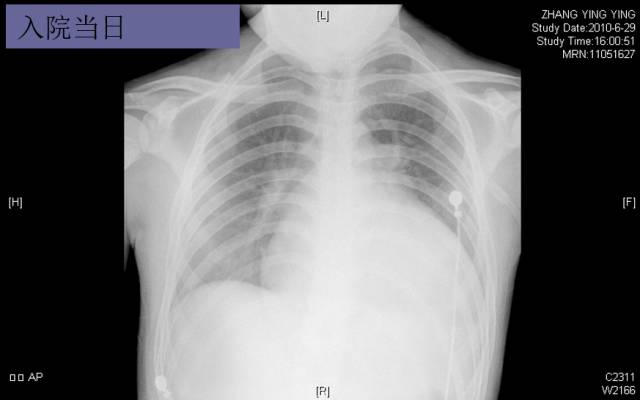

入院胸片